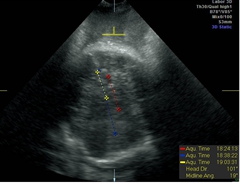

GE公司的SonoVCAD labor技术是基于三维容积超声的计算机辅助产程监测软件。利用三维超声多平面成像技术,可同时显示相交平面,增加了更多信息,使得测量的切面更为准确,重复性佳[5]。软件可在三维容积数据的不同平面自动测量出相应的胎头方向角(图1)、胎头进展角(图2)、胎头下降距离(图3)及中线角(图4)这四个参数,并在产程中动态观察各参数的变化,利用软件记录产程的全过程(图5),从而监测第二产程进展。

图4.在B平面上描记胎头的中线,中线角为胎头中线与耻骨联合下缘垂线的夹角